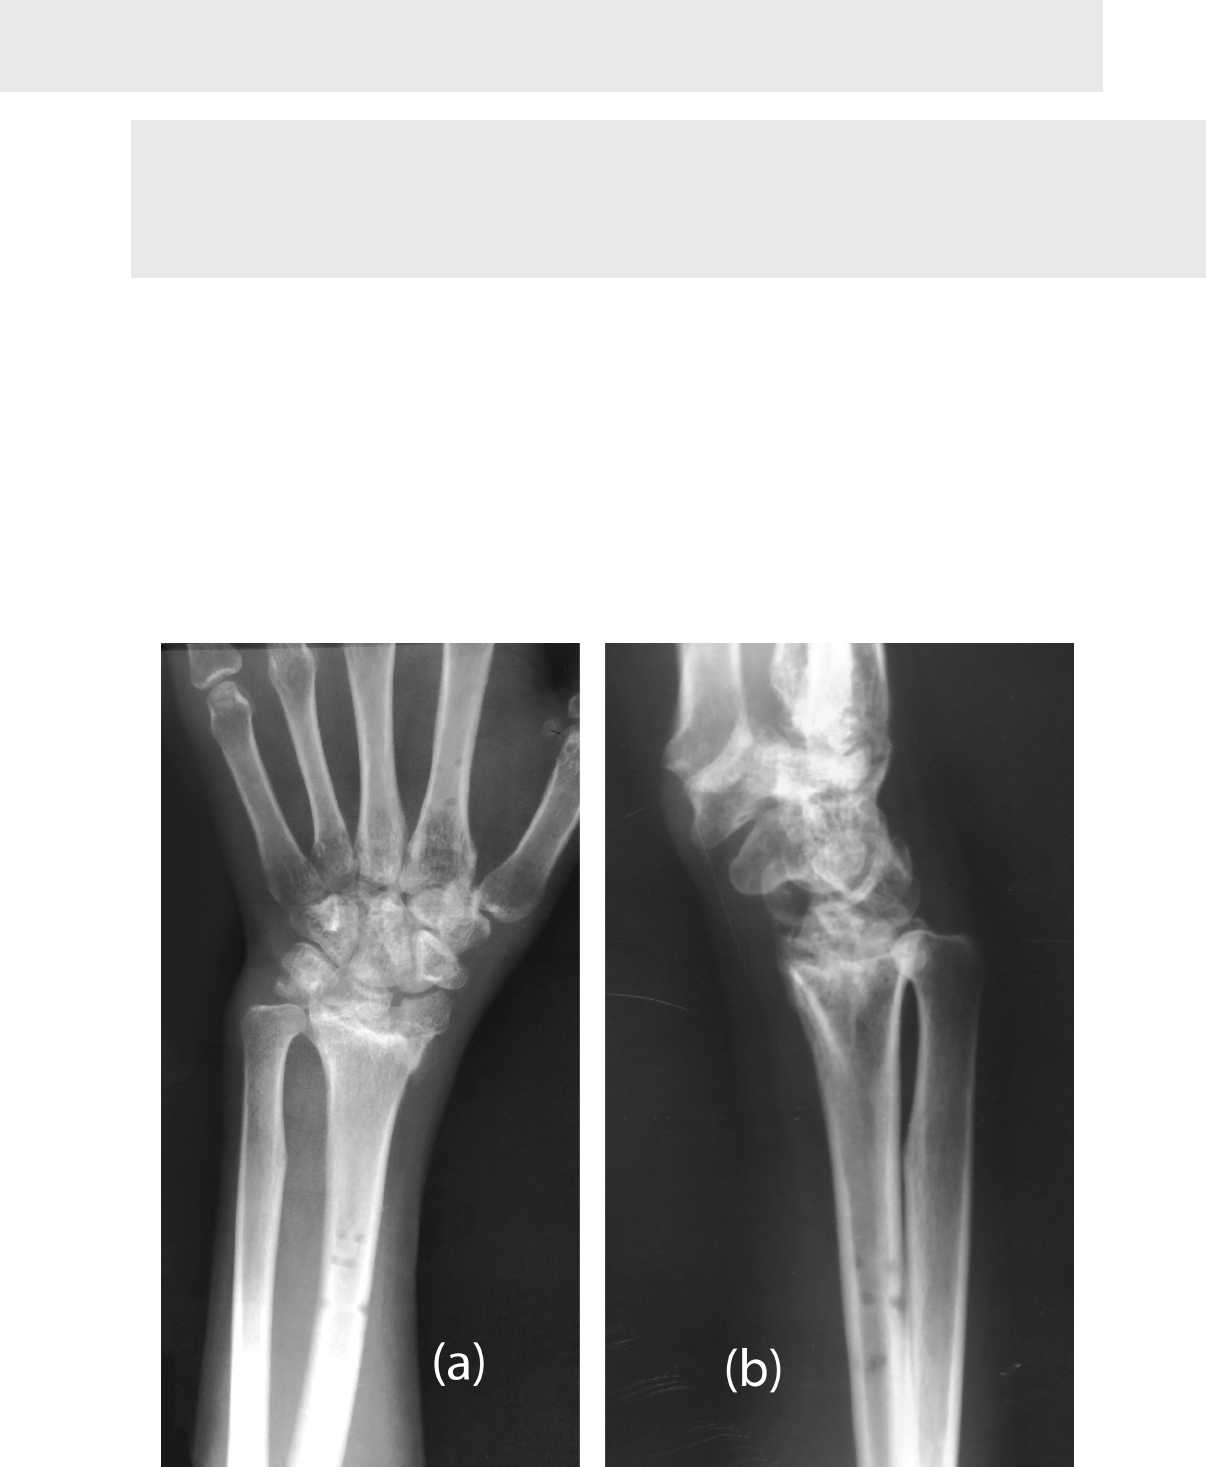

Grátis: Fratura de Punho - Material Claro e Objetivo em PDF para Estudo Rápido

Fratura do rádio distal: Manipulação sob anestesia (MUA) e fixação com fio K-overview - OrthOracle